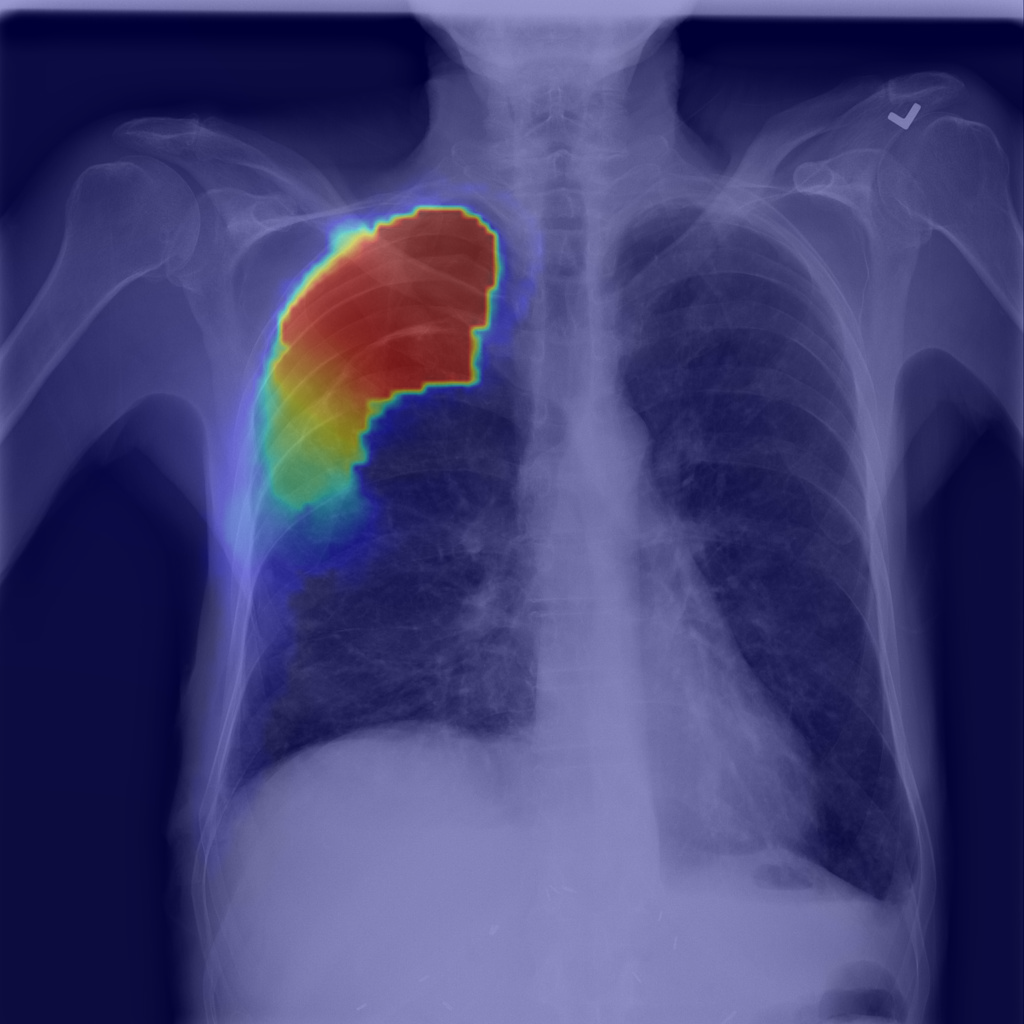

Refer to caption

(b) Step1.CAM

Figure 1: Pneumothorax localization maps for (a) a random image from the test set at each consecutive step of our method: (b) map after CAM extraction, (c) improved map by IRNet trained on the outcomed of step 1, (d) prediction of U-Net trained on step 2 results, all compared to (e) ground truth mask.

We present method’s explainability via disease localization regions; cf. Figure 1. We provide qualitative results of segmentation on validation images from both datasets in Figure 2 and Figure 3. We show the resulting maps at each step of our method; the figures demonstrate how the performance improves after each step. We achieve comparable results to state-of-the-art method on PASCAL VOC 2012; cf. Table 4.